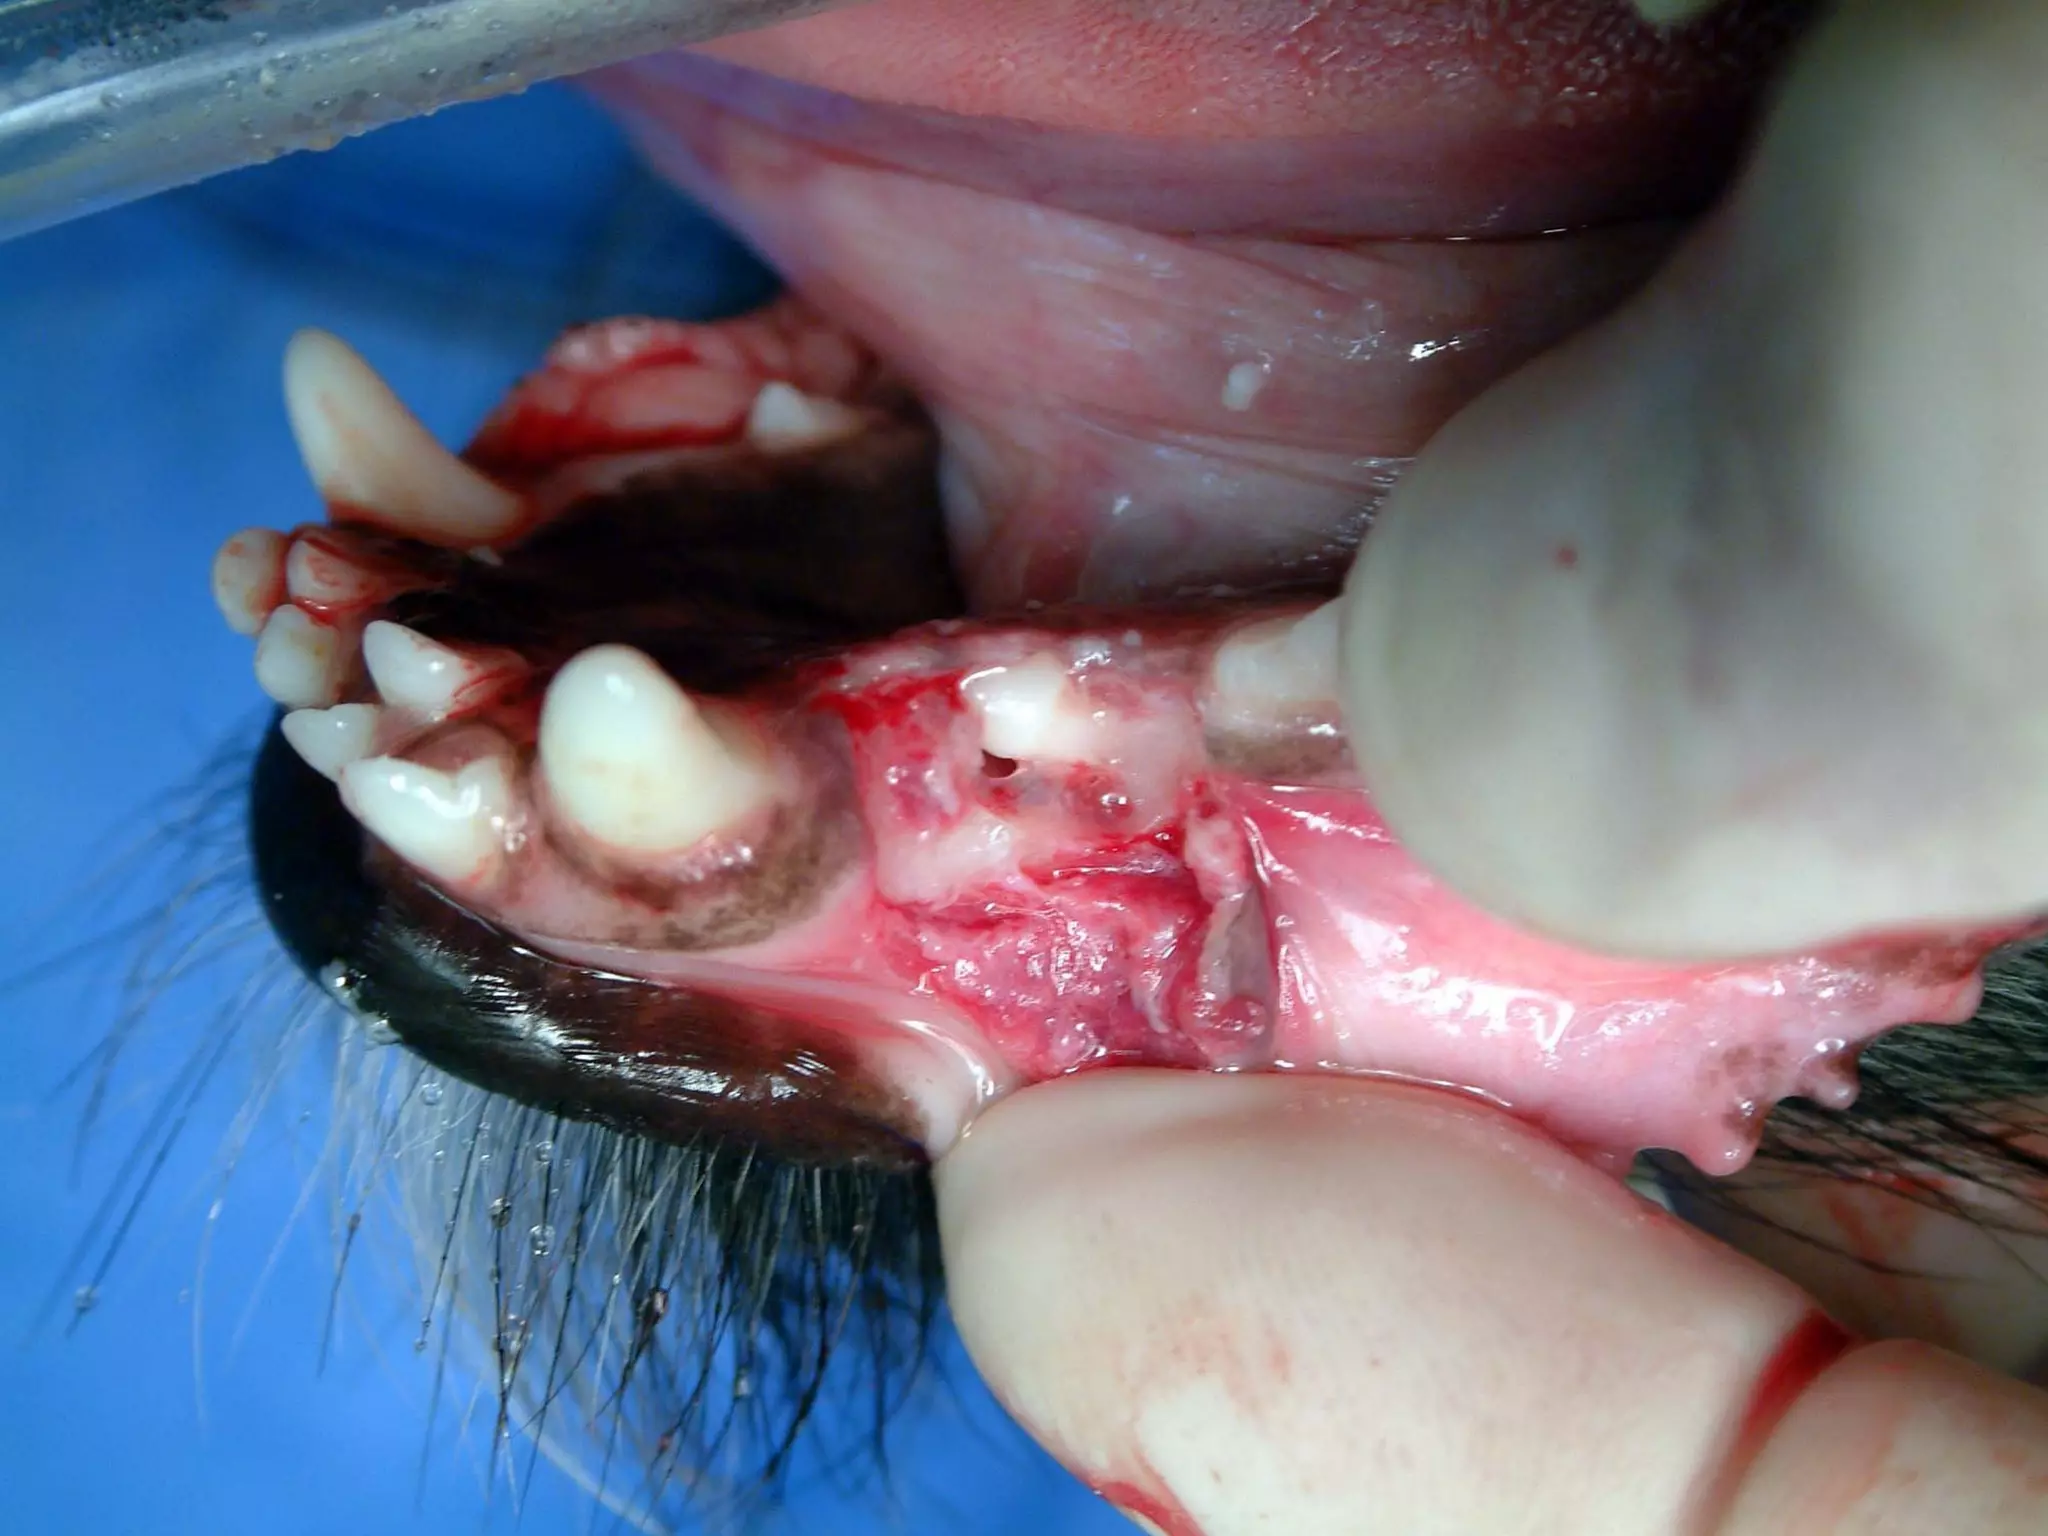

What is the disease present here?

Anatomical description of the

affected tooth?

38

What is thedisease present here? Anatomical description of the affected tooth? 38